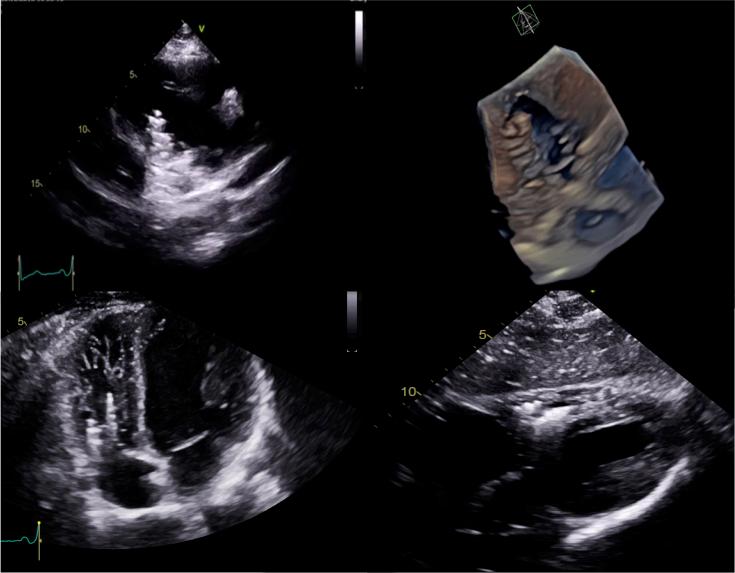

We describe a case of an adult patient with embolization of a varicocele coil (7 × 70 mm) to the right ventricle. We review the multimodality imaging techniques used to identify location and the importance of a multidisciplinary approach in determining management. ().

我们描述了一例成年患者,其精索静脉曲张线圈(7×70毫米)栓塞至右心室。我们回顾了用于确定位置的多模态成像技术以及多学科方法在确定治疗方案中的重要性。()